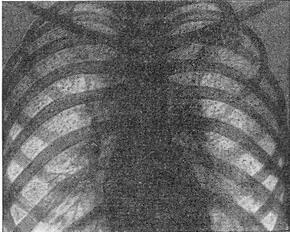

![]() Рис. 2. Міліарний туберкульоз. |

При легеневій формі уражаються головним чином легені (рис. 2). Слід враховувати, що рентгенологічно міліарні вогнища виявляються з 2-3-го тижня захворювання. Аускультативно визначається розлитої бронхіоліт з розсіяними сухими і мізерними вологими хрипами. Спостерігається виражена задишка і ціаноз. Ці ж симптоми характерні і для тифоидной форми, яка по тяжкості течії схожа з черевним тифом. Селезінка при милиарном туберкульозі різко збільшена, м'яка. При менингеальной формі виступають на перший план головні болі при високій температурі і характерні менінгеальні симптоми. Для підтвердження діагнозу менінгіту необхідна спинномозкова пункція.